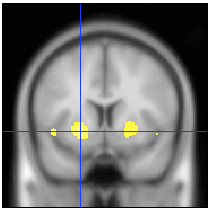

Données VBM comparant un groupe de personnes âgés par rapport à un groupe jeune lors d’une tâche de lecture July 8, 2014 • 213 × 213 • Multimédia Like Loading...